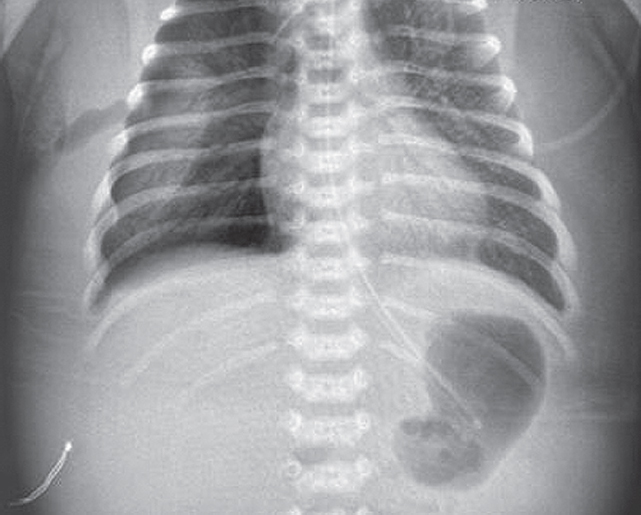

The article presents a case of successful treatment of acute respiratory distress syndrome in a full-term newborn complicated by pulmonary barotrauma using monobronchial administration of exogenous surfactant under X-ray control. In order to assess the course of the disease and the effectiveness of treatment, a retrospective analysis of medical documentation was carried out. From the first minutes of life, the child had respiratory disorders, which was the basis for non-invasive mechanical lung ventilation — nCPAP (nasal continuous positive airway pressure). Progression of hypercapnia and hypoxemia was revealed over time, and therefore tracheal intubation was performed and convective mechanical ventilation was started with FiO2 = 1,0. Monobronchial administration of exogenous surfactant was a key element of the therapy that allowed to achieve stabilization of the condition and regression of gas exchange disorders with complete recovery of the patient.